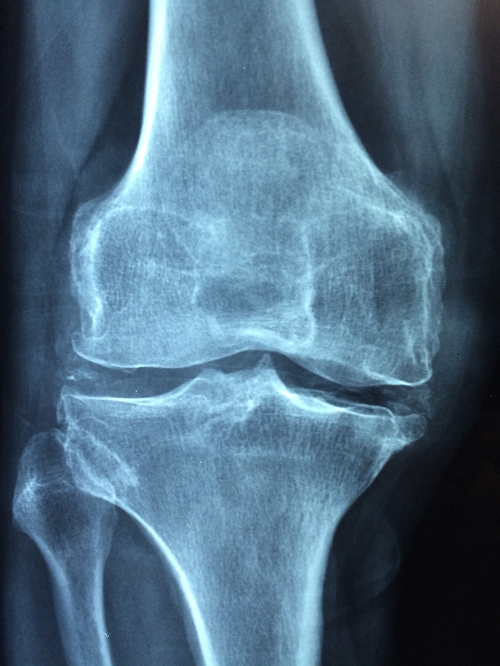

골다공증은 뼈의 밀도가 감소하여 뼈가 약해지는 질환으로, 노년기에는 특히 위험합니다. 골절이나 척추 압박 골절과 같은 심각한 부상을 초래할 수 있기 때문에 예방이 매우 중요합니다.